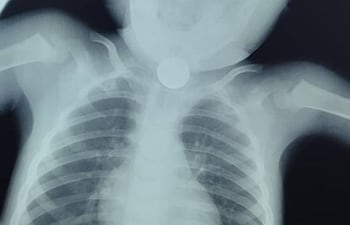

El doctor Carlos Morínigo, neumólogo del Instituto Nacional de Enfermedades Respiratorias y del Ambiente (Ineram), reportó que este año ya le tocó intervenir en cuatro casos de niños que tragaron monedas. Por esto, el exministro de Salud pide a los padres una mayor atención en el cuidado.

Los niños son los que generalmente sufren más casos de atragantamiento, seguidos por los adultos mayores y, finalmente, personas de todas las edades que se exponen especialmente al no tener en cuenta algunos aspectos que se debe cuidar para evitarlos. Te contamos las consecuencias de un atragantamiento y qué hacer en caso de que ocurra.